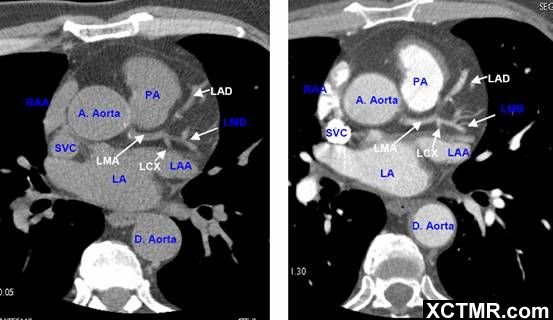

心脏CT解剖中英文对照标注(一)(图文)

常用英文名称及缩写 LA - Left Atrium 左心房 RA - Right Atrium 右心房 LV - Left Ventricle 左心室 RV - Right Ventricle 右心室 Mitral Valve 二尖瓣 A. Aorta-Ascending Aorta 升主动脉 D. Aorta-Descending Aorta 降主动脉 SVC – Superior Vena Cava 上腔静脉 IVC – Inferior Vena Cava 下腔静脉 PA - Pulmonary Artery 肺动脉 PV - Pulmonary Vein 肺静脉 LMA - Left Main Artery 冠状动脉左主干 LAD - Left Anterior Descending Artery 左前降支 LCX - Left Circumflex Artery 左回旋支 LMB - Left Obtuse Marginal Branch 左边缘支(钝缘支) RCA - Right Coronary Artery 右冠状动脉 PDA - Posterior Descending Artery 后降支 Conus Branch 右动脉圆锥支 LAA – Left Atrial Appendage 左心耳 RAA – Right Atrial Appendage 右心耳 CS - Coronary Sinus 冠状窦 MCV – Middle Cardiac Vein 心中静脉 GCV –Great Cardiac Vein 心大静脉 PIVV – Posterior Intraventricular Vein 后室间静脉(心中静脉) PLVV – Posterior Left Ventricular Vein 左室后静脉 PLV – Posterior Lateral Vein 左室后侧静脉(边缘静脉) | |